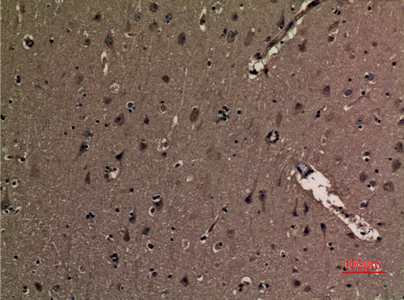

Immunohistochemical analysis of paraffin-embedded human-brain, antibody was diluted at 1:100